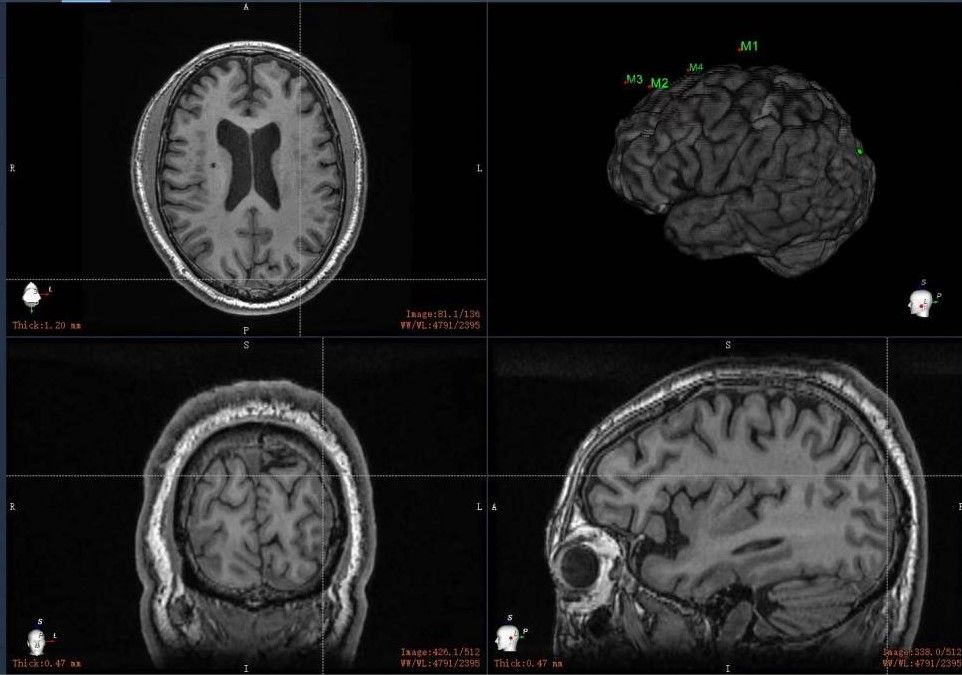

2023.6.20日上午张良文教授、张春普教授带领团队成员进行第一期手术,手术通过神经外科导航机器人进行术前及术中导航定位,确保刺激电极放置准确,手术过程顺利将电极植入了患者运动皮层的硬膜外(图1-3),术后复查再次确认电极位置准确(图4)。术后第2天开始进行临时体外电刺激,逐步对患者进行程控调整刺激参数,患者右侧面部及躯体疼痛明显缓解,疼痛评分(VAS)由术前的9分逐步降至了术后的5分,且无不适感。患者术前因为下肢疼痛不敢下地行走,术后也明显的改善了!几天后团队又为患者在局麻下第二期植入了永久的电刺激器。

图4:术后复查显示电极位置准确。